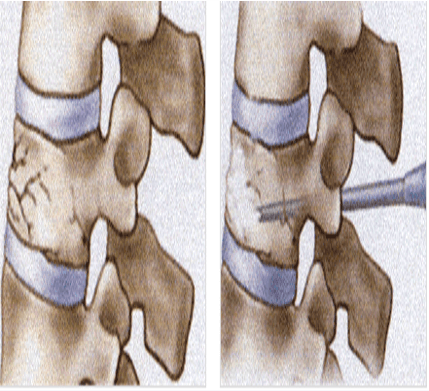

척추 성형술은 척추 뼈가 더 이상 주저 앉는 것을 최대로 막고 초기 단계에서는 주저앉은 척추뼈를 다시 펴 줄 수 있는 시술입니다.

국소 마취만 하고 엎드려 누운 상태에서 C-arm이라는 X-ray 기계로 척추 뼈를 보면서 시술이 필요한 척추 뼈 안으로 특수 바늘을 넣고 이 바늘을 통해 뼈 강화제(골 시멘트)를 넣어 줍니다.

척추성형술과는 달리 바늘을 통해 직접 골 시멘트를 주입하는 대신 척추 뼈의 양측에 특수한 풍선을 넣어 부풀리면서 주저앉은 척추 뼈를 펴주고 뼈 안에 골 시멘트가 들어갈 수 있는 충분한 공간을 만든 후 골 시멘트를 주입하는 시술 방법입니다.

이 시술은 척추성형술에 비해 주저앉은 척추 뼈 높이를 보다 많이 펴주고 골 시멘트가 신경 쪽으로 새는 것을 막아주며, 척추 뼈의 뒤쪽이 깨져 있거나 틈이 있는 경우에 시행하게 됩니다.